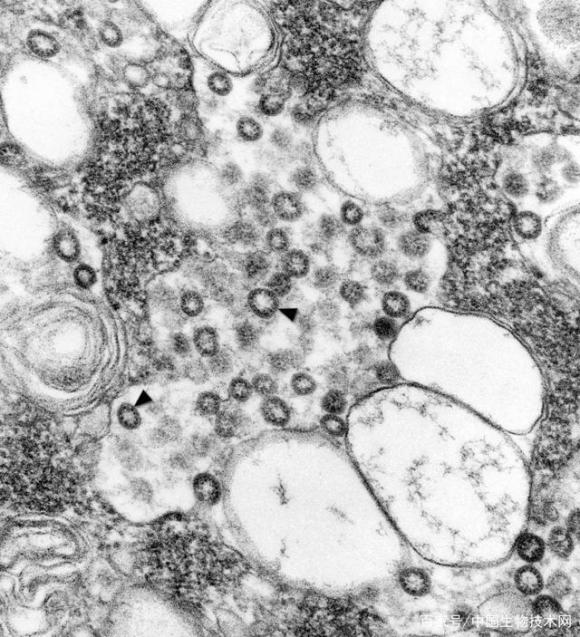

透射顯微鏡圖像:暗黑色圓形物的為新冠病毒。

NIAID表示,新冠病毒的圖像看起來(lái)和2012年暴發(fā)的MERS病毒以及2002年出現(xiàn)的SARS病毒很相似,這并不奇怪,因?yàn)檫@類病毒表面的突起物讓其擁有了“冠狀(corona)”的名稱,是“王冠(crown)”的拉丁文,所以,所有冠狀病毒基本都有這樣的形態(tài)特點(diǎn)。